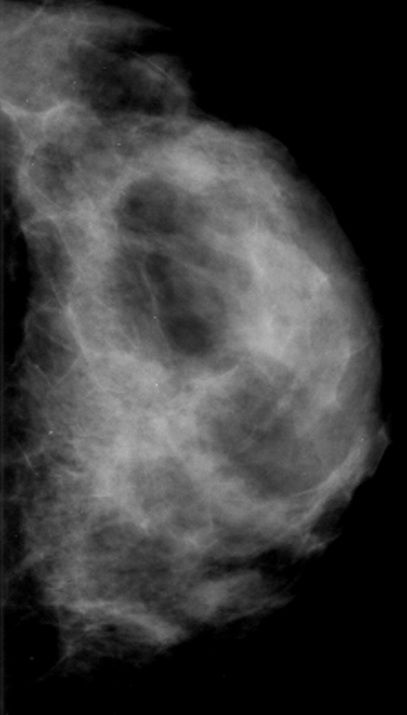

What’s your diagnosis?